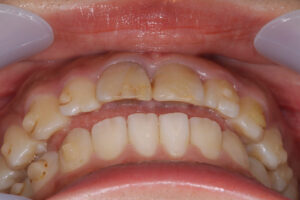

初診時に前歯が噛んでいない

インビザラインで失敗した23歳女性

初診時に奥歯が噛んでいない

ワイヤー矯正で全体の歯が噛んでいる